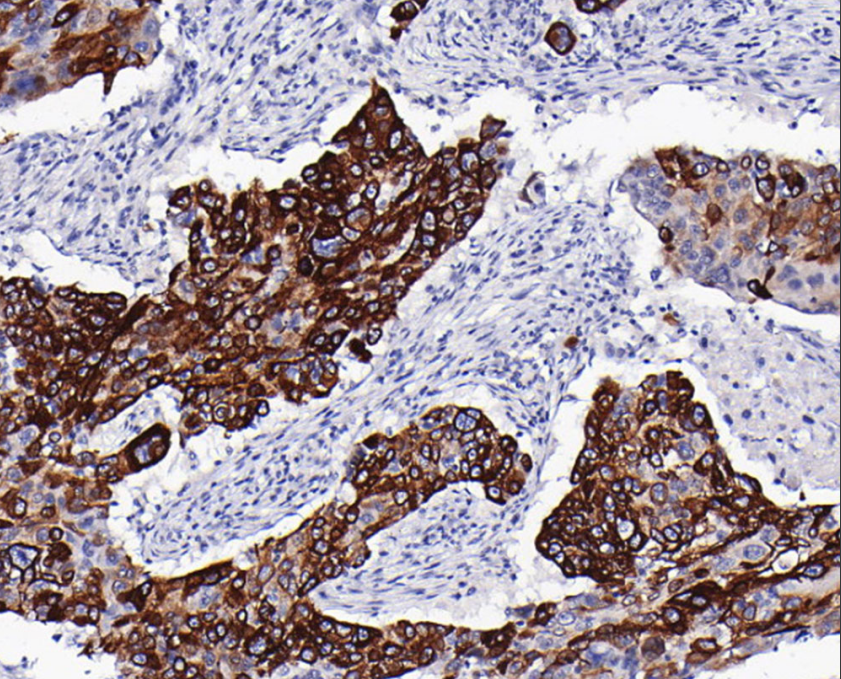

Cellular localization: cytoplasm/membrane

Positive control: skin/lung squamous cell carcinoma/cervical squamous cell carcinoma

CK15 is predominantly expressed in basal keratinocytes of complex epithelia and is mainly used in the diagnosis of squamous carcinoma.

CK15 antibody reagents can specifically bind to CK15 molecular antigens. Immunohistochemistry kits containing CK15 antibody reagents are suitable for the auxiliary diagnosis of squamous cell carcinoma.